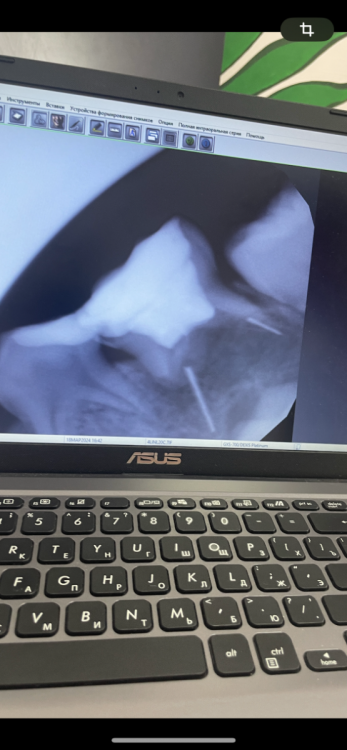

Niksvey Опубликовано 22 марта, 2024 Поделиться Опубликовано 22 марта, 2024 Все события происходят в рамках одного года При первом осмотре нам было сказано: 5.1 5.2 5.4 6.1 7.5 8.4 Пульпиты, 6.4 удаление Начинается процесс лечения зубов, где врач предлагает убрать 5.4 из-за невозможности его уже вылечить. После удаления двух зубов, рекомендуют консультацию ортодонта, где врач заключает, что в ближайшее время делать ничего не нужно. Продолжаем лечение оставшихся зубов. После пролечивания всех зубов каждые 1,5 месяца ходим на прием и чистки. Спустя 2-3 месяца Из зуба 5.5 постоянно вылетает пломба, у нас меняется врач, который говорит пломба держаться не будет, заболит зуб- удалим Попадаем мы уже к другому врачу, которая спустя несколько месяцев предлагает спасти 5.5, посмотрев снимки. В десне был гной, его убирают, назначают антибиотики и пролечивают зуб. (Почему другие два стоматолога не хотели его нормально пролечить я не знаю) Начинает болеть 5.2 его удаляют Через 2 недели появляется свищ на 5.1 его удаляют Меняем стоматологию Через две недели свищ на 6.1 его удаляем, где на осмотре нам говорят, что в зубе 8.4 свищ и его нужно удалять, а в зубе 7.5 два обломка инструмента, его тоже удалять Итого за год, за время лечения в этой стоматологии -1 зуб с которым мы пришли, и 6 удалили после лечения Лечение пульпита проводилось без коффердама Хочу услышать мнение, теперь ребенку трудно жевать и откусывать пищу, нам сказали что передние зубы не скоро прорежутся, а жевательные тем более и рекомендуют поставить пластину. Есть ли здесь вина стоматологии в том, что у нас три свища и в одном зубе обломки инструмента? То есть как минимум 4 зуба удалены из-за некачественного лечения. Ребенок не болел отитом или простудами, откуда взялись свищи? Можем ли мы расчитывать на компенсацию? Ссылка на комментарий